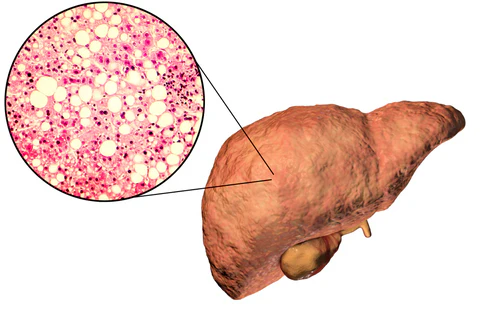

Manakala fruktosa ini tidak digunakan oleh mana-mana sel dan ia dibawa terus ke hati. Apabila ianya dicernakan di hati, ini yang akan menyebabkan banyak masalah. Oleh itu, setiap individu perlu berhati-hati dengan pengambilan fruktosa tidak semulajadi.

Selain itu, lebih menakutkan 70-80% fruktosa akan ditukar menjadi Very Low Density Lipoprotein atau VLDL yang mana akan ini merupakan komponen yang menyebabkan obesiti.

Disamping itu, fruktosa juga boleh menghasilkan titisan lipid di hati yang boleh menyebabkan berlakunya sindrom hati berlemak dan boleh menyebabkan kerosakan hati. Ia juga boleh mengganggu nitric oxide pathway di dalam darah. Nitric oxide ini penting untuk pengembangan salur darah.

Jika paras nitric oxide rendah, salur darah akan menjadi sempit dan meningkatkan risiko darah tinggi. Ia juga boleh menyebabkan rintangan insulin meningkat seterusnya menyebabkan penyakit Diabetes.

Selain itu, fruktosa yang dihadam di hati boleh menghasilkan bahan-bahan kumuh seperti asid urik. Dalam kehidupan moden hari ini semua makanan kita mengandungi fruktosa.